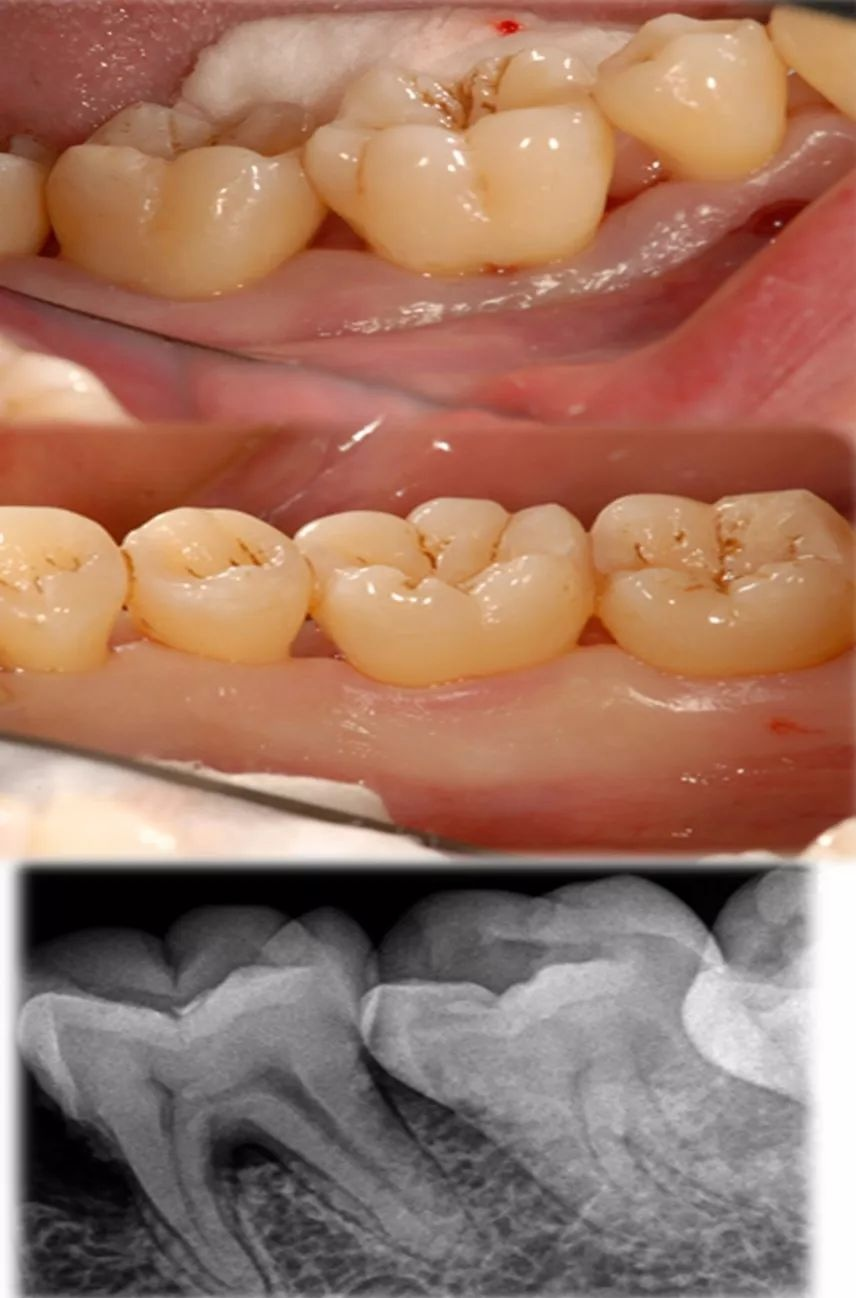

牙周炎本身不是传染病,但致病菌(如牙龈卟啉单胞菌)可通过唾液传播,有家族聚集倾向。